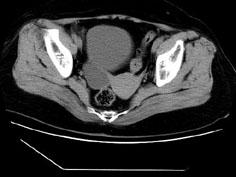

问题 女性,27岁,体检时B超发现右侧附件区囊性占位性病变,行CT检查,下列说法错误的是 ( )

选项 A、此为卵巢浆液性囊腺瘤 B、此为卵巢囊肿 C、病灶边界清晰 D、病灶为单房,壁薄,无分隔 E、病灶来源于右侧卵巢

答案 A